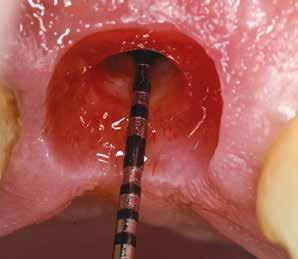

Az eljárást helyi érzéstelenítés mellett végeztük (4%-os articaine-hidroklorid 1:100 000 adrenalinnal). Papillakímélő, U alakú palatális bemetszést végeztünk, teljes vastagságú nyálkahártyalebeny preparálás történt, a lebenyt bukkálisan feltekertük (5. ábra). A lebeny bukkálisan feltekert részén de-epitelizációt végeztük el, amellyel kompenzálni tudtuk a bukkális lágyszöveti defektust. Szakaszos előfúrást végeztünk, és a bredent copaSKY 4x10 implantátumot 30 Ncm behajtási nyomatékkal helyeztük be (6. ábra). Az implantátumot 1 mm-re szubkresztálisan helyeztük be, hogy később szélesebb emergenciaprofilt tudjunk kialakítani (7. ábra). Az egyedi ínyformázó úgy készült, hogy kompozitot vittünk fel a titánbázisra, és így formáztuk a lágyszöveteket a transzgingivális gyógyulási fázis során (8. ábra). Az egyéni ínyformázó tulipán formájú, hogy kialakítsa a kívánt emergenciaprofilt. A lágyszövetet feszülésmentesen zártuk #6/0 nem felszívódó, monofil fonallal (Optilene, B. Braun Deutschland; 9. a–b. ábra). Posztoperatív röntgenfelvétel készült, ami alapján az implantátum a szomszédos fogakkal párhuzamos elhelyezést mutatott (10. ábra). Posztoperatív utasításokat adtunk a páciensnek a műtéti terület körüli szájhigiénia fenntartása érdekében. A beavatkozást követő egy héttel a varratokat eltávolítottuk, és a kezelt terület kielégítő gyógyulást mutatott (11. ábra). A 4 hónap utáni késleltetett terhelést a páciens kívánsága szerint terveztük.

volt megfigyelhető (13–14. ábra), ezen kívül közvetlenül a műtét előtt intraorális vizsgálatot végeztünk a lágyszöveti profil megállapítása érdekében. Ezt követte a scanbody behelyezése, így digitális lenyomat készült az implantátum pozíciójáról (15. ábra). Ugyanezzel a technikával rögzítettük az antagonista fogívet és a harapást is. Az így kapott STL-fájlokat digitálisan továbbítottuk a fogtechnikai laboratóriumba. A titánalapra PMMA ideiglenes koronát készítettünk a proximális és marginális illeszkedés ellenőrzése érdekében, valamint a megfelelő harapás elérése céljából (16–17. ábra) Miután az összes igazítás elkészült, ismételt vizsgálatot végeztünk. A végleges hibrid csavarrögzítésű, teljes kontúrú cirkóniumkoronát titánalapon erősen polírozott szubgingivális résszel készítettük el, és 25 Ncm nyomatékra húztuk (18. ábra). Kiváló árnyalategyezést és klinikai eredményt

15. ábra: Az intraorális szkennelést több lépésben végeztük, hogy regisztráljuk az íny lefutását, illetve a scanbody segítségével meghatározzuk az implantátum pozícióját. 16. ábra: Az elkészült ideiglenes PMMA korona.